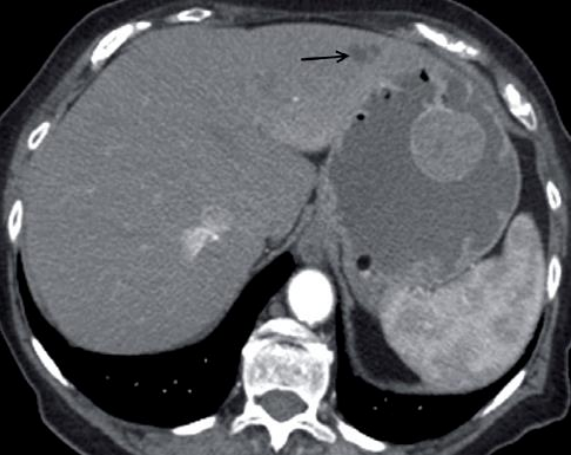

Observe a imagem abaixo. Paciente apresenta perda de peso, dor epigástrica e anemia.

Diante do exposto, é INCORRETO afirmar que